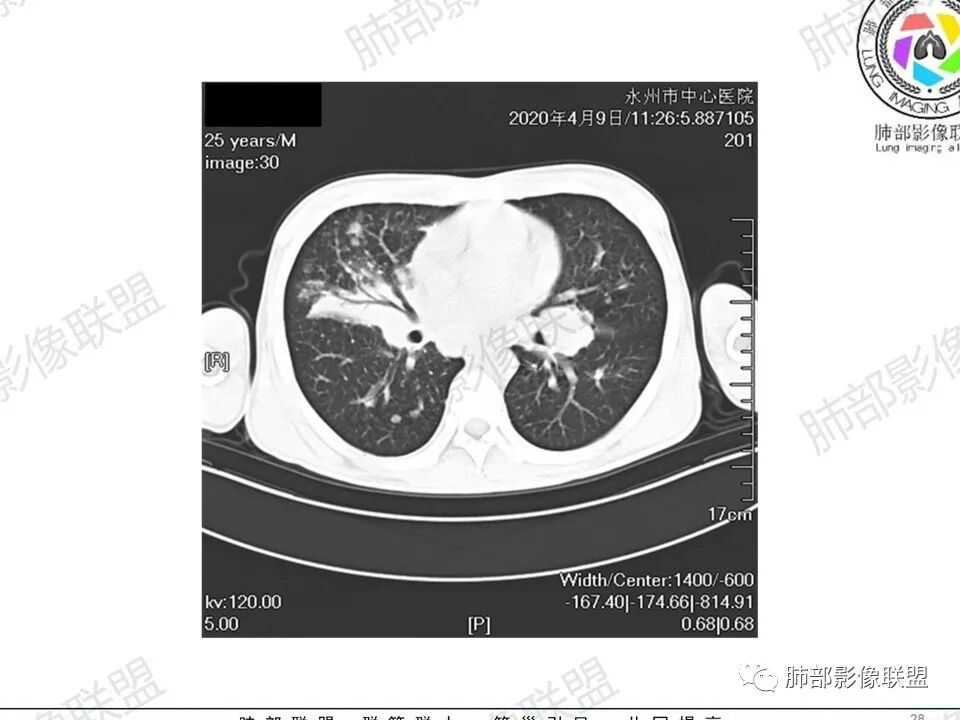

那个人:青年男性,慢性病程,咳嗽气促,伴盗汗胸痛。实验室,贫血,血沉快,C反应蛋白升高,低蛋白血症。影像,双肺散在斑片影,结节影,伴树芽,斑片影源支气管血管束分布,支气管走形自然,结节影有小空洞,有些周围有磨玻璃成分,小结节有些成串珠样改变,纵隔肺门淋巴结肿大,心腔低密度。考虑淋巴增值类疾病,结核?淋巴瘤?结节病?鉴别血管炎,实验室,影像不太支持

一切∮随缘:双肺多发大小不等结节,结节密度高,边缘清楚,部分结节内可见血管穿行,另右肺长条状实变影,内部可见支气管充气征,局部支气管壁增厚,双肺多发小树丫,双肺门及纵隔淋巴结肿大,部分融合,无增强,对淋巴结坏死无法判断,临床:年轻男性慢性病史急性加重,血象、CRP、ESR高,考虑一元论:结核(年龄加影像都符合),二元论:结节病或淋巴瘤+结核(建议CT增强及淋巴结穿刺),无原发肿瘤病史,癌性淋巴管炎代排。

男性,25岁,咳嗽咳痰1年,气促两月,加重一天,伴盗汗胸痛。CT示双肺散在斑片影,结节影,树芽征,部分周围伴磨玻璃影,以右肺上叶明显,纵隔及双肺门可见多发淋巴结肿大,部分融合,青年人,病史较长,首先考虑结核,不排除结核合并结节病可能。

3、影像表现:双肺散在斑片影及结节影,部分结节内可见血管穿行,斑片影沿支气管血管束分布,近胸膜侧病变收缩不明显。部分中央淋巴间质增厚,小叶间隔增厚。病灶内支气管穿行,部分支气管略扩张。局部小结节呈串珠样改变。纵隔、肺门区、锁骨上及腋窝淋淋巴结肿大,部分有融合。心腔低密度。脾大。

2.双肺多发片影及结节影,边界可分辨,右肺中上叶较为密集,没有胸膜下分布优势。病灶实性密度为主,未见钙化及液化。

3.右肺较多微小结节,密度较为浅淡,部分沿血管束分布,未见沿小叶间隔及叶间裂分布结节影,未见典型的终末气道树芽。

4.病灶区域穿行支气管显示良好,未见壁增厚及管腔狭窄。

5.双肺门及纵隔淋巴结显著增大,这改变相当显眼。这里强调“双肺门”及“多发”!

增大的淋巴结密度偏低且均匀。此外患者有体表淋巴结增大。

淋巴瘤肺部浸润表现多样,多发结节影是其最常出现的影像学改变,尤其是霍奇金病。

2.右肺多发微小结节影,部分沿血管束分布,尽管未见小叶间隔改变,但双肺门淋巴结增大确实应当首先排除结节病,但经验上说,结节病的增大淋巴结密度往往较高、较密实,边界往往清楚,“独立性”很强,绝无“融合之嫌”!此外,较少出现贫血、脾大,临床表现也往往较轻微。